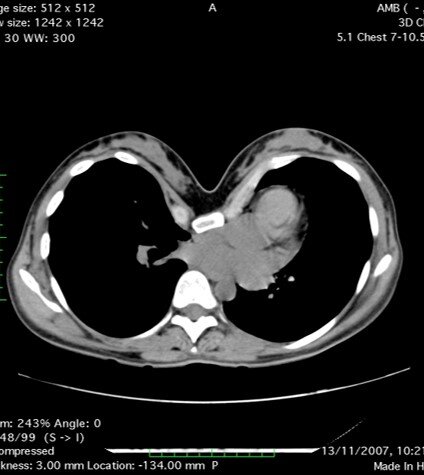

Мы имеем собственный опыт по лечению пациенток с ВДГК, которые благополучно беременели, вынашивали и рожали до коррекции деформации и после.

За период 2004-2018 9 женщин в возрасте 23-41 благополучно беременели, вынашивали ребенка и рожали. 5 пациенток рожали до коррекции (1 роды 2-е, 2 родов – 2 и 3 – 1) - группа 1, и 6 пациенток забеременели после коррекции с установленной пластиной/пластинами (группа 2), из них у 4 беременность развилась впервые, у 2-х беременность и роды были уже и до коррекции.

Период беременности не имел каких-либо особенностей в обеих группах. В первой группе беременность закончилась естественными родами во всех случаях. В группе после коррекции с установленной пластиной/пластинами беременность наступала через 1 месяцев после коррекции (2), 1 год (2) 2 года (1). За время беременности каких-либо особенностей или дополнительных жало в области грудной клетки не отмечено. В 2 случаях было проведено кесарево сечение и в 4 – естественные роды.